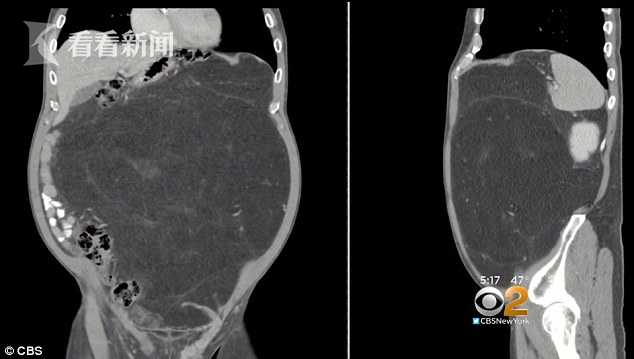

直到去年12月,越来越觉得不舒服的戴利,说服了他的医生为他做了一次CT扫描,结果发现腹部有一个12磅重(约10斤多)的肿块。 戴利说,这个发现让他感到他的担心是正确的和令人害怕的。

根据扫描的影像,深灰色中心区域显示的是戴利腹部内的肿瘤 ,这种被称为脂肪肉瘤的恶性肿瘤可能已经生长了10到15年 。幸运的是,这个恶性肿瘤并没有在戴利体内转移。